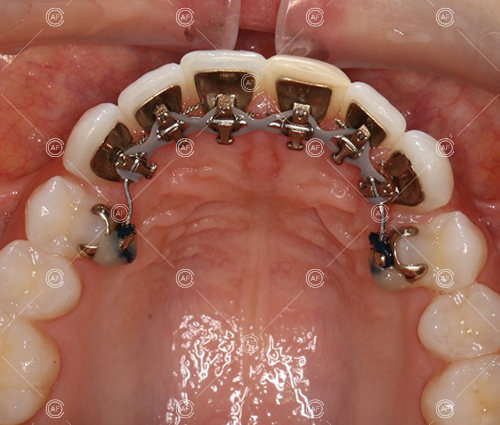

Treatment progressed by starting with thin, flexible nickel titanium archwires of a round diameter, transitioning to a rectangular nickel titanium archwire before eventually working up to a working archwire (1925 stainless steel).

Residual space from the extractions were closed using upper and lower nickel titanium closing coils. Class 2 elastics were used to facilitate space closure in order to gain class 1 buccal segments.